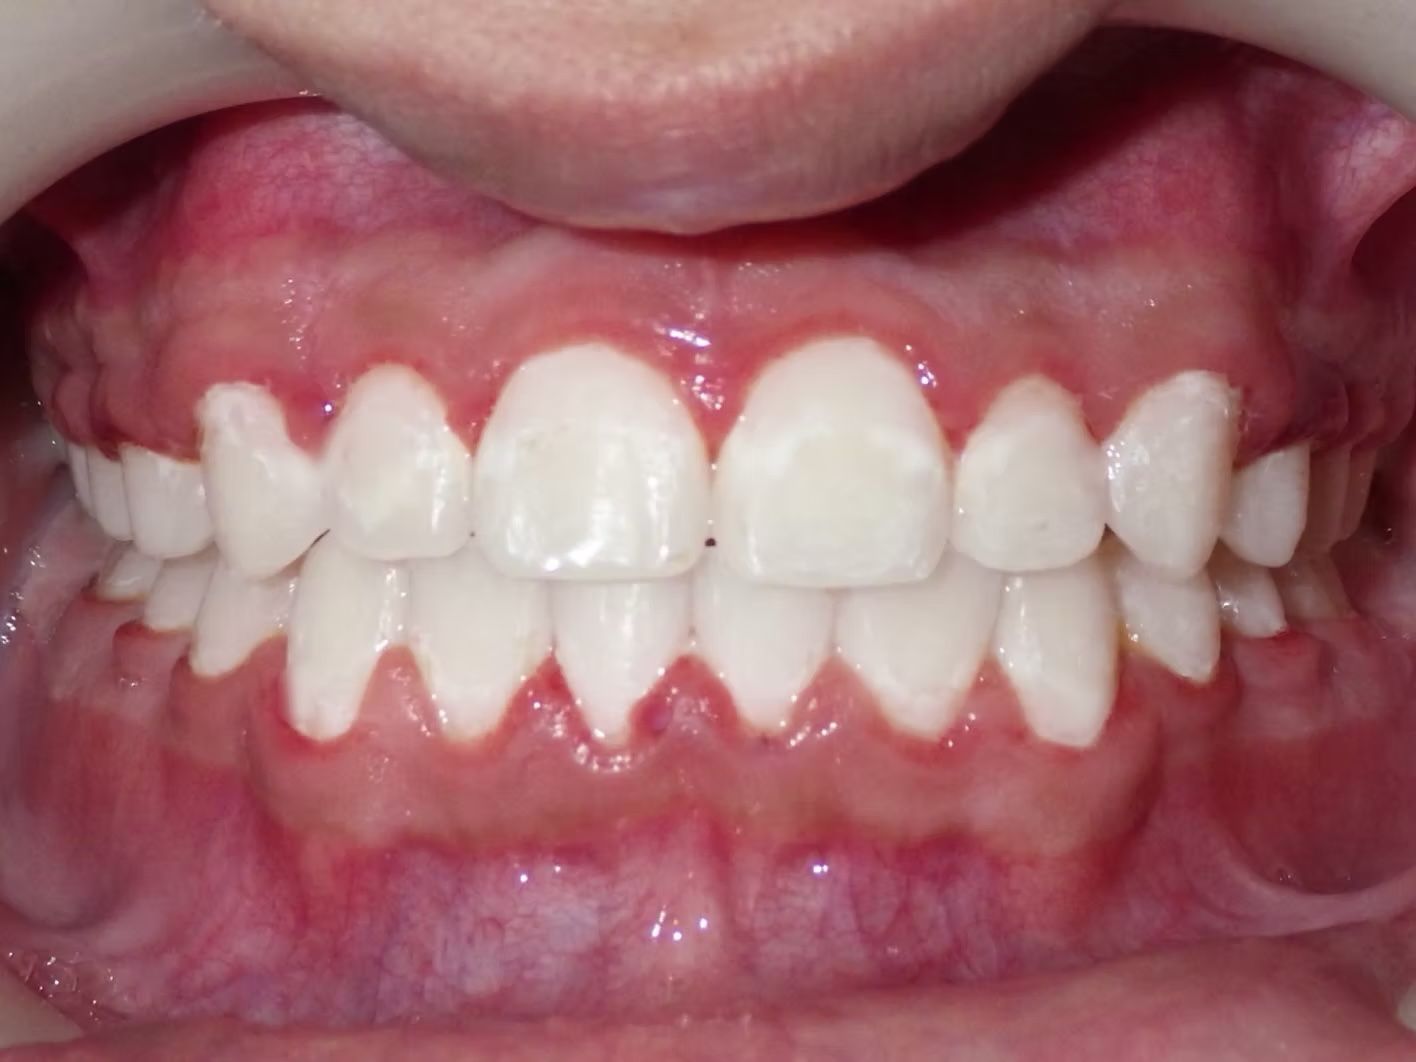

AMBER

Amber, began treatment with Dr. Bret because she didn't like that her front teeth overlapped each other. She had narrow top and bottom dental arches with severe crowding of her upper and lower teeth. She was treated with braces on the upper and lower teeth, and we used the braces to widen the smile. What a change!